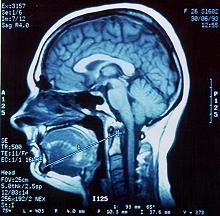

Resonancia magn tica nuclear

(ID 1732)

Resultado de la resonancia magn tica nuclear

(ID 2010)